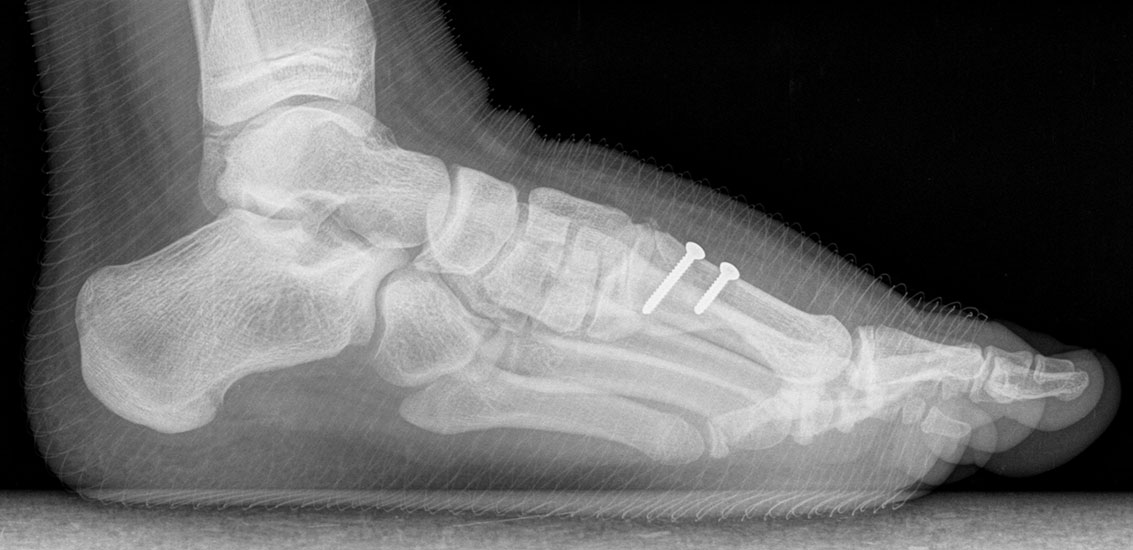

Bezüglich der Operationstechniken wird von früher häufig durchgeführten alleinigen Weich­teileingriffen am Großzehengrundgelenk aufgrund hoher Rezidivraten abgeraten 15. Die Operation nach Mc Bride mit lateralem Release, Exzision des lateralen Sesambeins, Abtragen der Pseudoexostose, Sehnenetransfer des M. adductor hallucis und mediale Kapselraffung zeigte unbefriedigende Mittel- und Langzeitergebnisse 16. Die Cerclage fibreux (mediale Kapselraffung) und das laterale Kapselrelease wird heute in Kombination mit einem knöchernen Eingriff angewendet. Bezüglich des Einsatzes von minimalinvasiven Operations­techniken vor Wachstumsabschluss liegen bisher keine Daten vor. Alle Osteotomien lassen sich nach Bedarf miteinander kombinieren. Es ist darauf zu achten, dass Osteotomien keine offenen Wachstumsfugen verletzen.

• Medial zuklappende Grundphalanxosteotomie nach Akin 17

• Subcapitale distale Chevron Osteotomie nach Austin 18

• Diaphysäre Osteotomie

• Scarf 19

• Ludloff 20

• Proximale Metatarsale I Osteotomien 21

• medial aufklappend – verlängernd

• lateral zuklappend – verkürzend

• bogenförmige Crescentic Osteotomie

• proximale Chevron Osteotomie

• proximale Verschiebeosteotomie

• medial aufklappende Cuneiforme I Osteotomie 1522

• Wachstumslenkung: Hemiepiphysiodese der lateralen Basisfuge am Metatarsale I  23

• Nach Schluss der Wachstumsfugen: TMT I Arthrodese nach Lapidus 2425